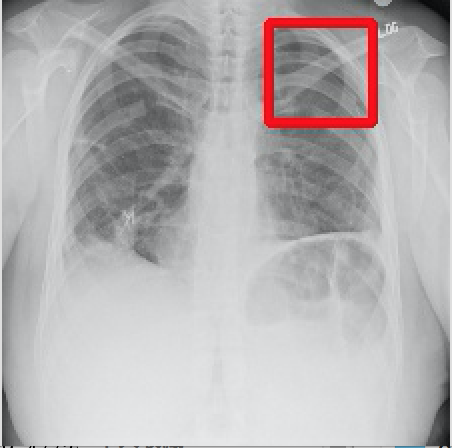

2017年CVPR的一篇“ChestX-ray8”论文[1]首次对医院留存的胸部CT数据库进行人工处理,并通过医学专家分别对8种疾病作标记,形成该领域首个标准的数据库,为胸部医疗的计算机辅助诊断打开了大门,也为后续的研究提供铺垫。CT数据库整理的效果如下图所示,其中红线框内为人工标注的疾病区域:

Atelectasis Cardiomegaly Effusion Infiltrate

Mass Nodule Pneumonia Pneumothorax

图2.1 胸部数据集示例

目前为止,数据集已经达到了14个疾病的分类结果,每张图的大小为1024×1024,少数图片附有由专家标注的病理区域,数据集共有112120张图片,来源于30805个不同的病人,其中51708张图片被标注有疾病,其余则为无病。可以看出无病的数据较多,对有病的特征学习可能较低,相关的学习加速收敛的方法将在2.4节讲解。